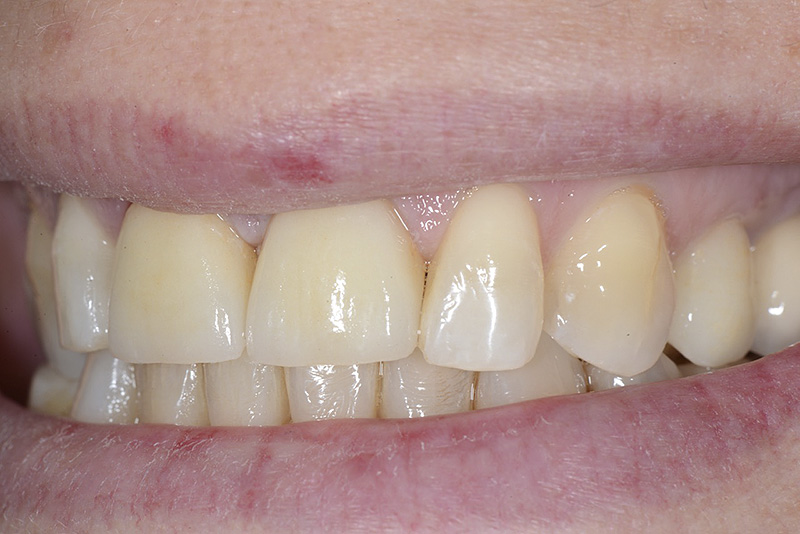

PREMESSA: in seguito all’estrazione dell’incisivo laterale superiore di destra, resasi necessaria per cause batteriche, si decide di affrontare il caso con il posizionamento di un impianto in sostituzione dell’elemento mancante dopo guarigione del sito infetto. Con tecniche rigenerative sia dei tessuti ossei mancanti a causa dell’infezione pregressa, sia dei tessuti gengivali che appaiono inizialmente troppo spostati in alto, si ripristina una corretta morfologia delle parabole (contorni) gengivali e delle papille interdentali (triangoli di gengiva tra due denti vicini).

Vengono utilizzati 2 tipi di provvisori: il primo, cementato ai denti vicini, viene utilizzato dal momento dell’estrazione del dente fino ad impianto osteointegrato (circa 6 mesi); il secondo, avvitato direttamente all’impianto, ha una funzione di prova estetica ma soprattutto di guida per la maturazione dei tessuti gengivali peri-implantari portandoli verso la maturazione completa prima di posizionare la corona finale in disilicato di litio.